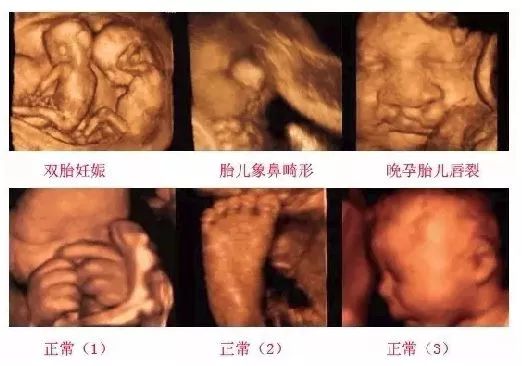

随着医疗技术的不断发展,B超系统作为一项重要的医学影像技术,已经在临床诊断中扮演着不可或缺的角色。本文将探讨B超系统在现代医学诊断中的应用及其重要性。

B超系统,全称为超声波诊断系统,是利用超声波在人体内传播、反射、折射等特性来获取人体内部组织结构信息的医学影像设备。B超系统主要由探头、主机、显示器和辅助设备组成。